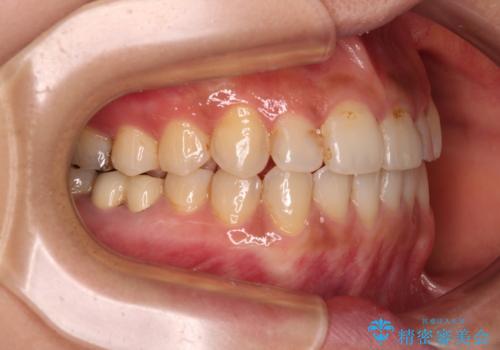

前歯のデコボコとクロスバイト インビザラインによる矯正治療

- 上下のクロスバイトと前歯のデコボコを気にして来院された患者様です。

骨格的に下顎がやや前方にあり、奥歯にクラウンが装着されているため、矯正治療後半の不安定な咬み合わせを避けるのであればワイヤー矯正がおすすめとなりますが、希望によりインビザラインにて治療を行うこととしました。

インビザラインを用い、IPR(歯と歯の間を削る)と歯列全体を拡大させることで、歯並びを整えていくこととしました。

懸念されたとおり、右下のクラウン部分が全く咬み合わず、仕上げの段階で治療期間が長くなりました。